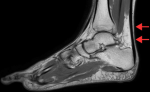

The Kager´s fat pad is an adipose structure located between the Achilles tendon, calcaneus, and flexor hallucis longus. Kager´s fat pad syndrome results from overuse, trauma, and underlying conditions like tendonitis. Pain and inflammation at the posterior side of the ankle are the primary complaints of patients with Kager´s fat pad syndrome. A 34-year-old male monk presented with posterior ankle pain, localized swelling, and reduced range of motion (ROM) that developed over several weeks. He had a history of barefoot walking and an ankle sprain sustained while climbing stairs two months earlier. Clinical examination revealed posterior ankle tenderness and dorsiflexion limitation. Magnetic resonance imaging (MRI) was ordered to confirm suspicions of ligamentous or soft tissue injury. Imaging demonstrated edema of Kager´s fat pad, sprain of the anterior and posterior talofibular ligaments, sprain of the calcaneofibular ligament, and retrocalcaneal bursitis. Kager´s fat pad pathology is a recognized but underdiagnosed source of posterior ankle pain, often seen in conjunction with other mechanical stressors. Imaging findings guided a conservative treatment plan consisting of cryotherapy, shockwave therapy, Maitland mobilization, taping, myofascial release, range of motion exercises, and strengthening exercises. The patient showed marked improvements in pain and ankle function over four weeks. This case supports prior findings that musculoskeletal imaging significantly enhances physiotherapy treatment planning.

Figure 1: sagittal T2-weighted MRI highlighting Kager´s fat pad syndrome (arrows) and associated retrocalcaneal bursitis